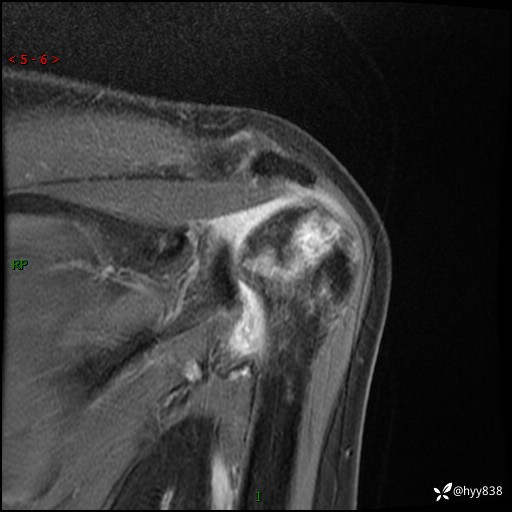

肱骨正侧位片

肱骨MRI平扫(axi T1WI+cor T2WI-fs)+CE-fs(COR+SAG)